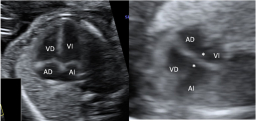

Corazón con canal atrioventricular

La imagen ecográfica muestra las cuatro cámaras de un corazón normal a la izquierda y de uno con canal atriventricular común (*) a la derecha. Ecografía Embarazo 2D y 3D Semana 20 - MALFORMACIONES FETALES Ecografía Embarazo 4D Semana 20 - MALFORMACIONES FETALES